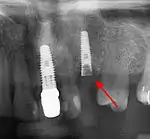

Bone loss (peri-implantitis) on implants over 7 years in a heavy smoker

Fixture show

Fracture of abutment screws (arrow) in 3 implants required removal of the remainder of the screw and replacement.